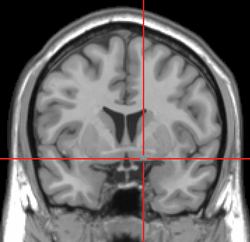

MRI showing a coronal plane of the head with marks showing the location of the substantia innominata, the region in which the nucleus basalis is found.

The NBM is inferior to the globus pallidus and within an area known as the substantia innominata. The NBM is immediately inferior to the anterior commissure and superior and lateral to the anterior portion of the hypothalamus.